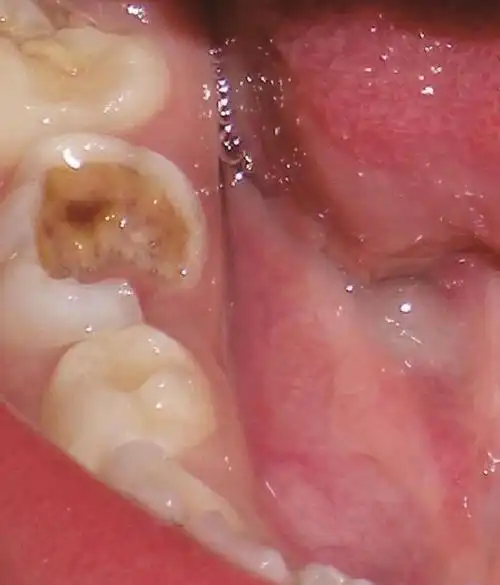

图18-9 s-ecc儿童广泛的右下第二乳磨牙龋坏及尚未完全萌出的右下第一